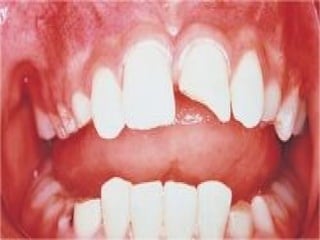

It is deviation from the normal orthodox tooth

shade. Although it is not destructive, yet it has a far-

reaching effect on the affected individual, both

socially and psychologically. According to its

etiology, discoloration can be either extrinsic due to

surface staining, calculus or surface deposits that can

be removed by proper scaling and polishing - or

intrinsic created from changes in one or more of the

tooth tissues.

 Discoloring changes of dentin may result either from

non-vitality or from pigmentation and staining e.g.

metallic restorations, medicaments, microbial

metabolites etc. Tetracycline discoloration

(tetracycline administered during tooth formation) is

a sort of permanent staining of dentin and to some

extent to enamel.